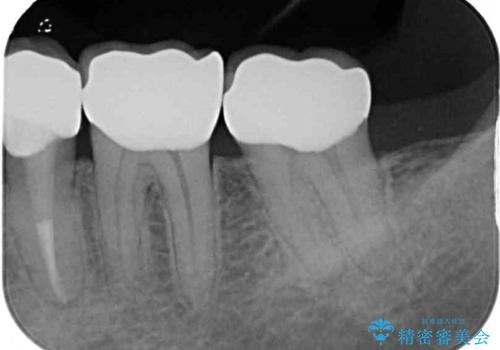

虫歯を取り除き、仮歯を装着した時点でしみる感覚は改善されました。

オールセラミッククラウン装着後も経過は良好です。